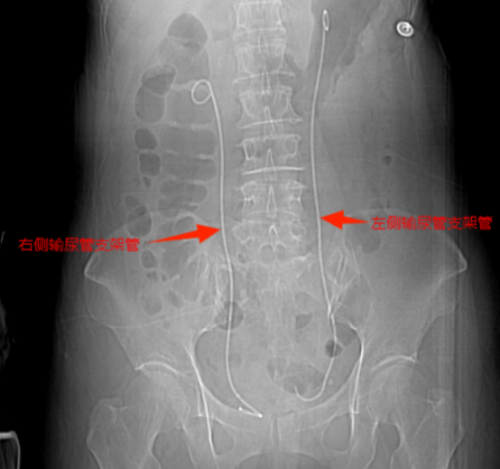

等到第二天送医时,张小华血压已降至78/42mmHg(血压<90/60mmHg称为休克血压),CT结果显示其双侧输尿管结石引发尿路梗阻,导致尿源性脓毒血症合并脓毒性休克。立博体育 立即启动MDT多学科诊疗,泌尿外科一区主任傅发军带领团队紧急在急诊ICU实施床旁输尿管支架置入术,迅速解除梗阻,经抗感染等综合治疗,患者最终转危为安。目前,张小华已康复出院,择期再返院处理双侧输尿管结石。

双侧输尿管支架置入后解除尿路梗阻